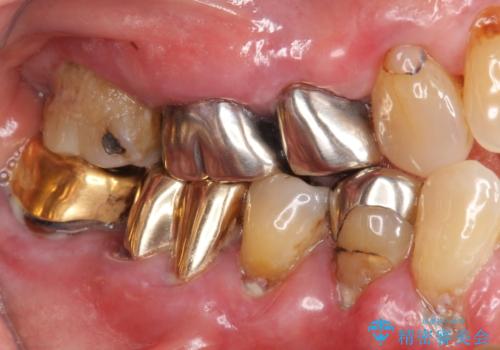

- 歯ぐきからの出血と腫れを主訴に来院された患者様です。

プラークコントロールが非常に悪く、全顎的な歯周病に罹患していました。

「抜歯したくない、インプラントは嫌」という患者様のご希望とご年齢を考慮し、可及的な骨外科処置や根分割術によりできるだけ今ある歯を残す治療方針をたてました。

保存不可能な左上の奥歯2本(左上67)は抜去し、ノンクラスプデンチャーをいれることにしました。